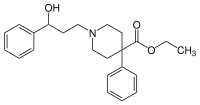

The first fully synthetic opioid was meperidine (later demerol), found serendipitously by German chemist Otto Eisleb (or Eislib) at IG Farben in 1932.[228] Meperidine was the first opiate to have a structure unrelated to morphine, but with opiate-like properties.[199] Its analgesic effects were discovered by Otto Schaumann in 1939.[228] Gustav Ehrhart and Max Bockmühl, also at IG Farben, built on the work of Eisleb and Schaumann. They developed "Hoechst 10820" (later methadone) around 1937.[230] In 1959 the Belgian physician Paul Janssen developed fentanyl, a synthetic drug with 30 to 50 times the potency of heroin.[211][231] Nearly 150 synthetic opioids are now known.[228]

Phenylpiperidines

- Pethidine (meperidine)